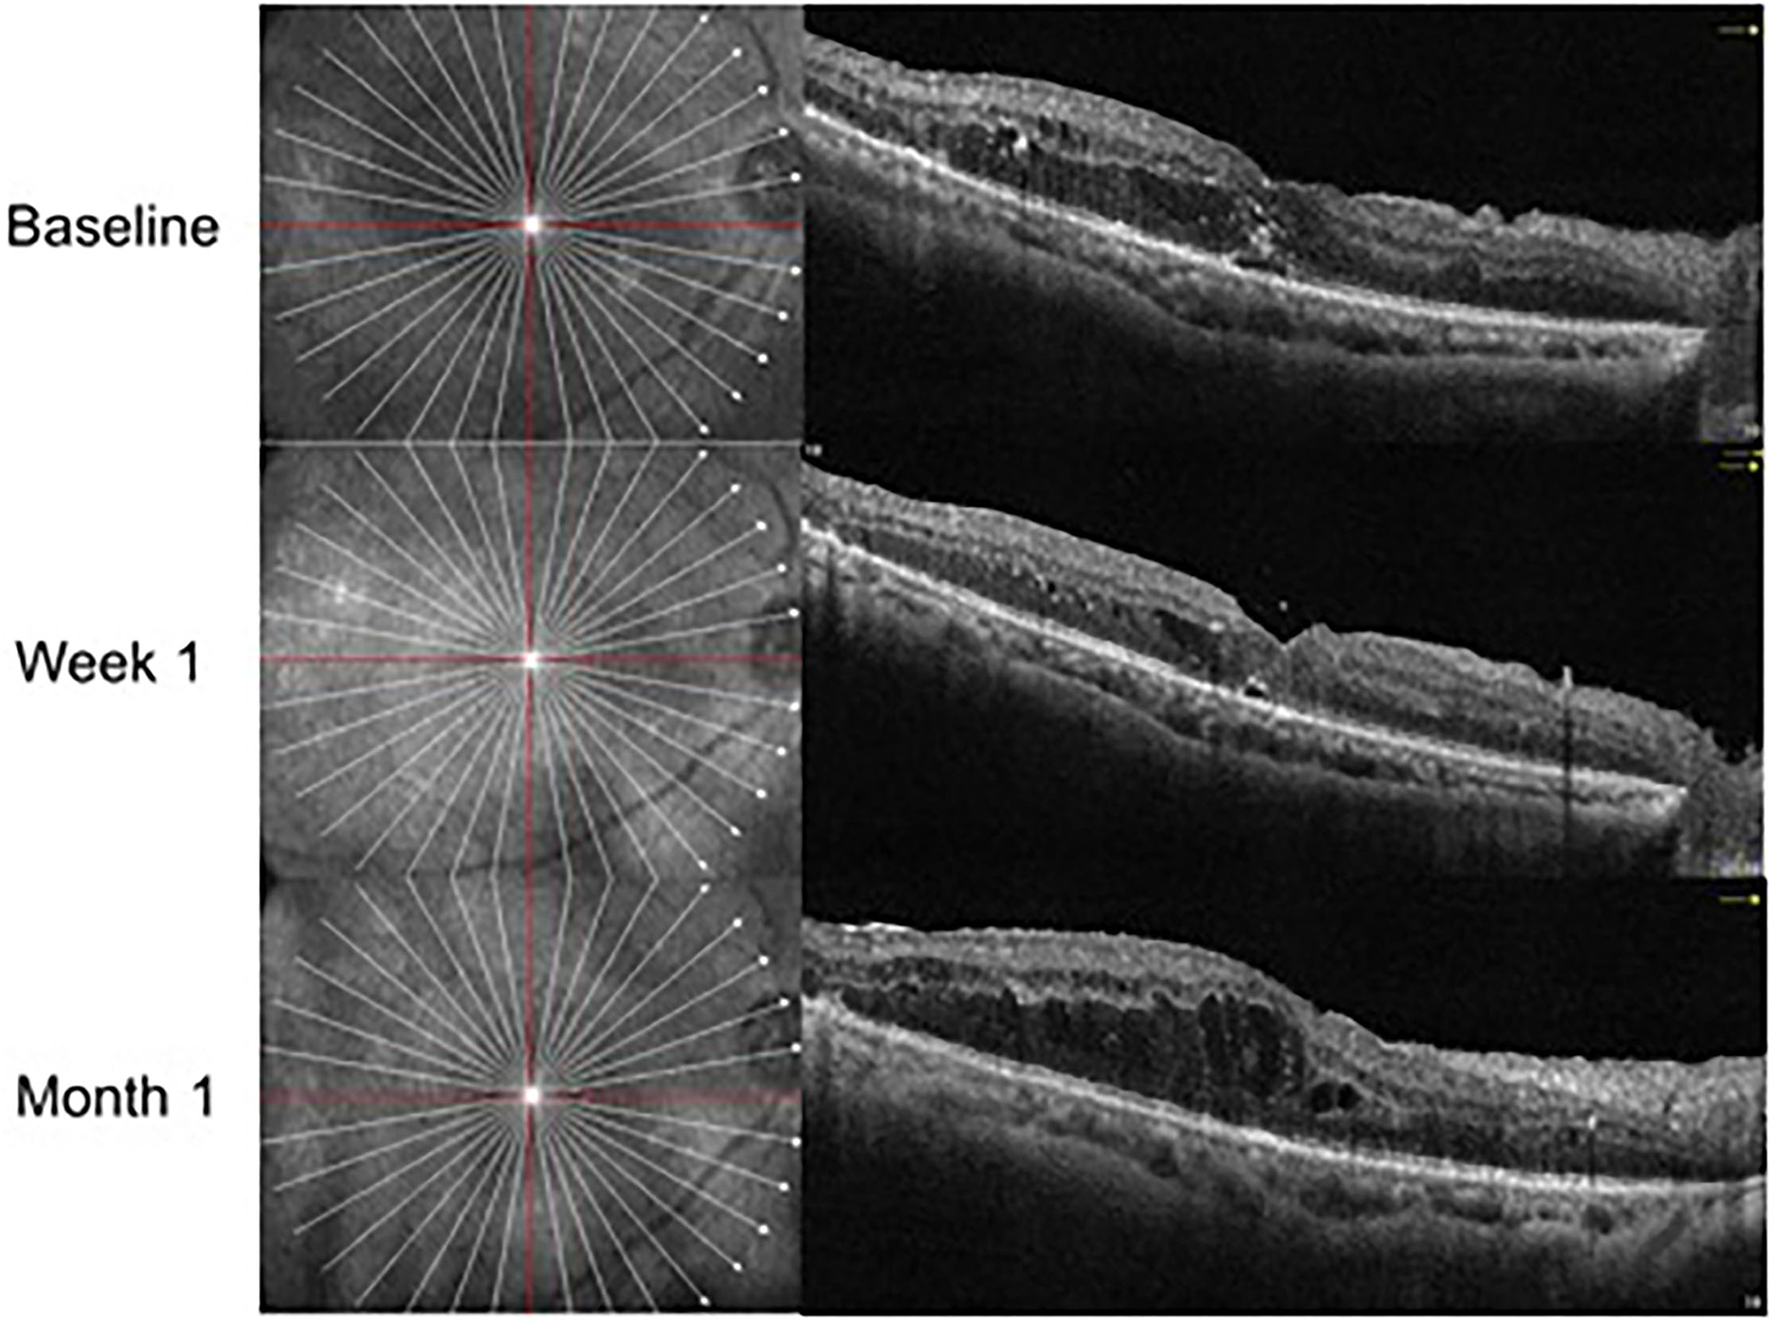

In the IVV group, the mean CRT was 398.88 ± 105.97 μm prior to injection, 333.53 ± 122.43 μm at Week 1, and 382.07 ± 105.49 μm at Month 1 (Figure 1). The changes in CRT were statistically significant at Week 1 but not significant at Month 1 (P = 0.041 and P = 0.170, respectively). A total of 35.3% of patients in the IVV group had a CRT decrease ≥ 20% at Week 1 and 31.7% at Month 1. 14.6% of patients had CRT worsening ≥ 20% at Month 1, but no patient had CRT worsening ≥ 20% at Week 1. The CRT in the IVD group at the baseline visit was 388.00 ± 104.71 μm, 310.45 ± 69.86 μm at Week 1, and 296.33 ± 48.73 μm at Month 1 (Figure 2). The changes in CRT within Week 1 and Month 1 were statistically significant when compared to the baseline values (P = 0.03 and P < 0.001, respectively). A total of 54.5% of patients in the IVD group had a decrease in CRT ≥ 20% at Week 1 and 62.5% at Month 1. No patient had CRT worsening ≥ 20% within 1 month (Table 3, Figure 3). The changes in BCVA and CRT between the 2 groups were statistically significant at Month 1 (Table 4).

Figure 1

OCT follow-up visit of the same patient with anti-VEGF treatment.

Figure 2

OCT follow-up visit of the same patient with Ozurdex treatment.